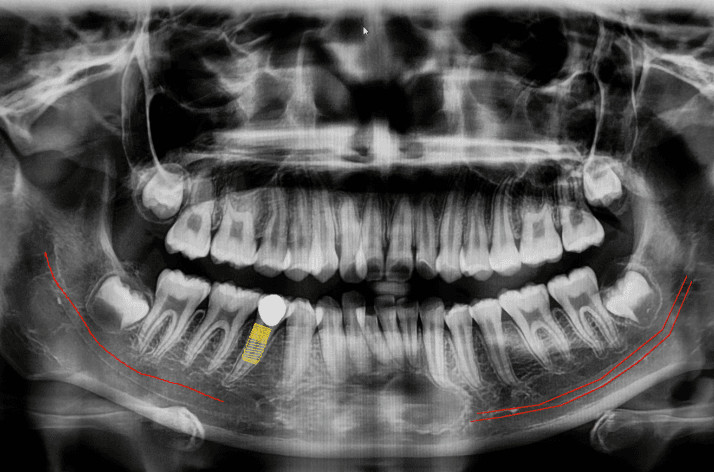

Panoramic X-Ray:  This is a type of sizeable dental X-ray that requires a separate machine. The X-ray provides a detailed image of all the teeth in both lower and upper arches, along with the bone and supporting structures. They are usually used for extensive dental work like multiple extractions, braces, dental implants, etc.

Some procedures, like the placement of dental implants, warrant the need for dental X-rays for the treatment to be carried out correctly.Diagnosis of developmental anomalies like cysts or tumors.Monitor the possibility of wisdom teeth getting impacted.In children, dental X-rays can be used to determine adequate space for erupting teeth.